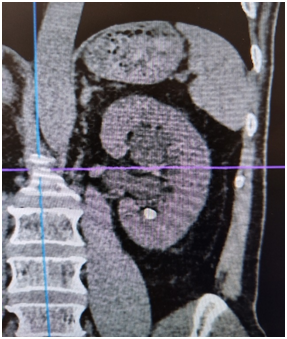

术前

输尿管鞘是什么名医动态|以柔克刚,无创取石——我院泌尿外科开展可弯曲负压吸引鞘+输尿管软镜钬激光碎石术_https://www.jmylbn.com_新闻资讯_第5张